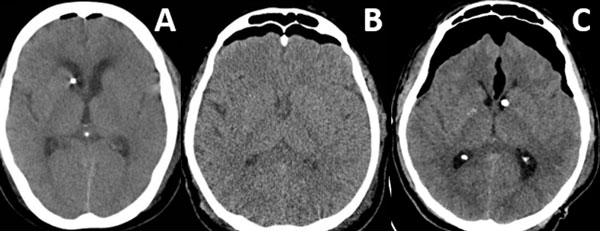

Patrones y grados de NE: NE subdural (Figura 1), se clasificó en 3 grados: leve (menor al espesor óseo), moderado (entre una vez y dos veces el espesor óseo) y severo (dos o más veces el espesor óseo). NE subaracnoideo (Figura 2), se clasificó en 3 grados: leve (confinado a cisternas basales), moderado (cisternas supratentoriales predominio unilateral), severo (generalizado). NE ventricular (Figura 3), se clasificó en: leve (en IV y/o III ventrículo), moderado (alcanzó VL), severo (alcanzó y dilató los VL).

Figura 1. Neumoencéfalo subdural. A) Leve. B) Moderado. C) Severo.